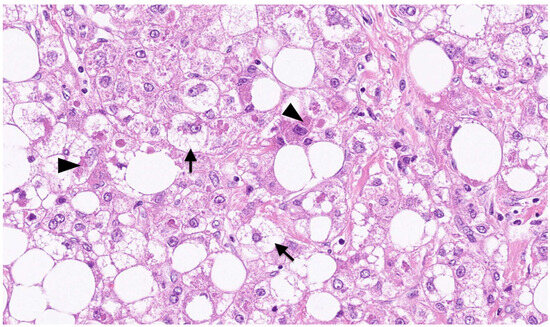

3.2. Pathological Features